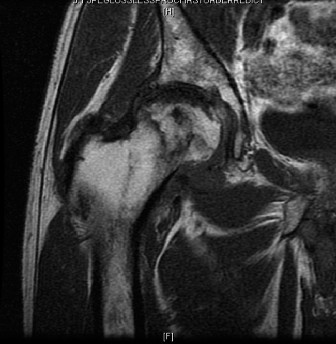

Magnetic Resonance Imaging (MRI) of the Right Hip:

- T1-weighted sequences: Showed low signal intensity in the femoral head, surrounded by a "double-line sign" on T2-weighted images, highly characteristic of AVN. The necrotic segment involved a significant portion of the superior and anterior weight-bearing femoral head (estimated >30% volume).

- T2-weighted and STIR sequences: Confirmed extensive edema within the femoral head and surrounding bone marrow, indicating active disease. Articular cartilage loss was evident superiorly, corresponding to the area of subchondral collapse. No significant soft tissue pathology, such as labral tears or abductor tendon pathology, was identified as a primary driver of symptoms, though secondary adaptive changes were noted. The MRI was critical in confirming the extent of necrosis, articular collapse, and evaluating the integrity of the surrounding cartilage and subchondral bone, confirming Ficat-Arlet Stage IV disease with secondary osteoarthritis.

Figure 1: Pre-operative MRI of the right hip demonstrating extensive avascular necrosis of the femoral head (Ficat-Arlet Stage IV) with characteristic double-line sign, significant subchondral collapse, and early secondary degenerative changes in the acetabulum.